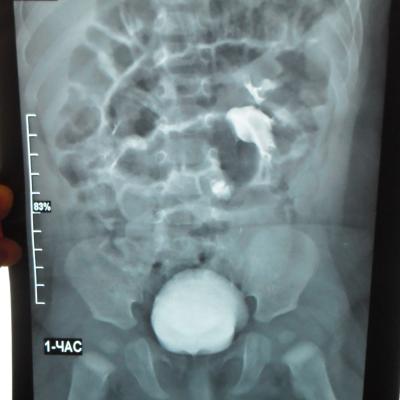

Моему ребенку 1 год 1 месяц. Во время беременности у плода было обнаружено увеличение лоханки слева - 9мм. Далее по результатам УЗИ после рождения максимальное увеличение достигало 17 мм. В 5 месяцев проходили урологическое обследование, результаты цистографии: мочевой пузырь округлой формы. Контуры ровные. ПМР нет. ЭЭД-1,2МЗВ; урографии: рентгеноконтрастных теней конкремента нет, почки в типичном месте, размеры сохранены, структура ЧЛК справа не изменена, слева пиелоэктазия, подвижность допустима, функция сохранена, ЭЭД – 0,4 МЗВ. По последнему УЗИ (1 год) увеличение лоханки слева - 28 мм. Мочеточники и сама почка в норме. Результаты анализов мочи за этот год хорошие (сдавали ежемесячно). В чем могут быть причины данного явления и чем это грозит малышу?

Ответ врача

В данном случае - сужение лоханочно-мочеточникового сегмента и\или добавочный сосуд(слева). Но выделительная функция почки сохранена. В данный момент целесообразно наблюдение, но в дальнейшем - не исключено хирургическое вмешательство.